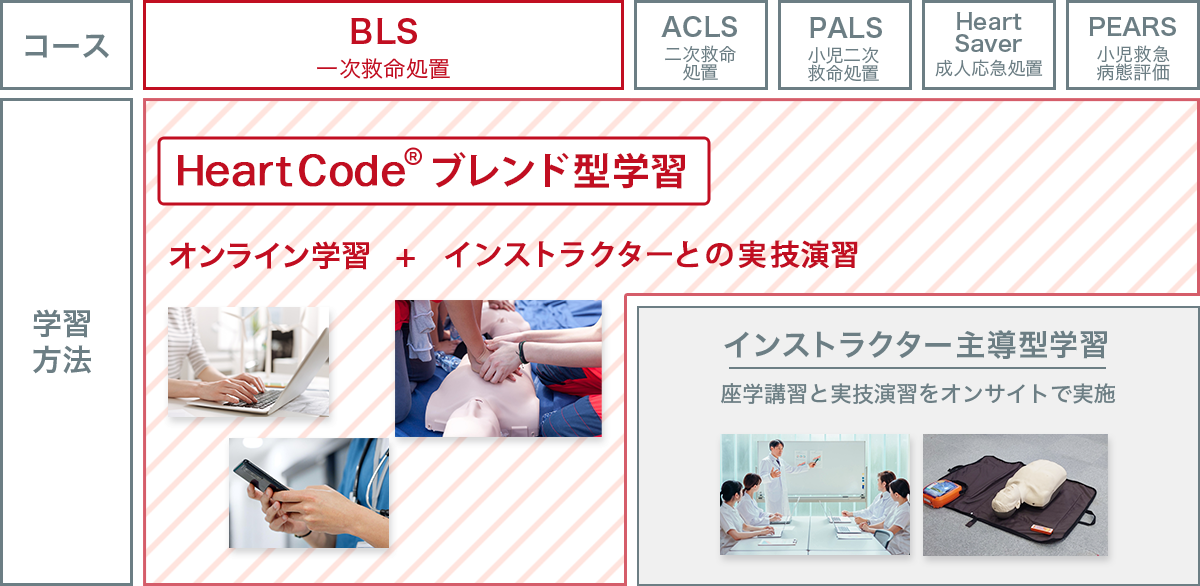

01

BLS以外のコースは引き続き

インストラクター主導型講習も実施

オンライン学習+実技演習のハイブリッド

BLS(一次救命処置)コースでは、

心肺停止に至るような生命を脅かす緊急事態を認識し、適切な胸骨圧迫や人工呼吸、AEDの使用法を中心に学習する。ガイドラインに基づく科学的知見と教育内容を反映しており、医療従事者および院内・院外を問わずさまざまな現場で心肺蘇生法のスキルを習得・実践する必要がある方を対象とする。